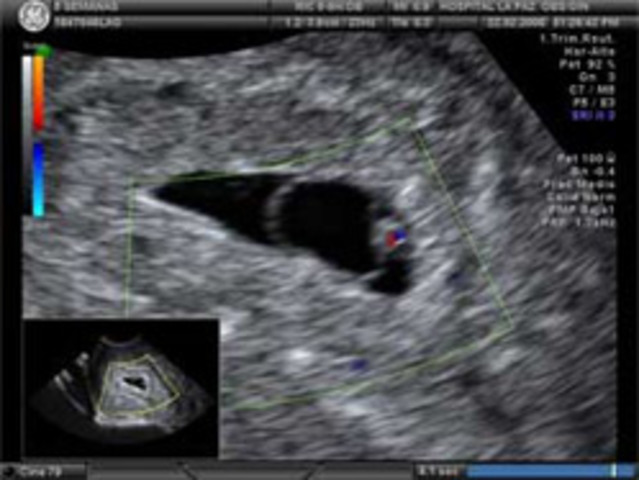

• Semana 9

Semana 9

Se forman los pezones y los folículos pilosos.

Los brazos crecen y se desarrollan los codos.

Se pueden observar los dedos del pie del bebé.

Todos los órganos esenciales del bebé han comenzado a crecer.